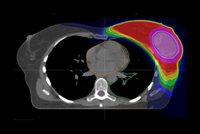

568. Kürzere Bestrahlungsdauer, gleichwertiges Behandlungsergebnis

Kürzere Bestrahlungszeit bei Brustkrebs durch integrierte Boost-Bestrahlung: Der Bereich der höchsten verabreichten Strahlendosis ist rosa markiert. Quelle: Universitätsklinikum Heidelberg Pressemitteilung des Universitätsklinikums Heidelberg (UKHD)